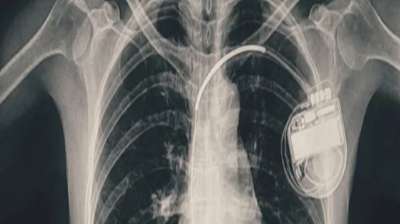

भोपाल के डॉक्टरों ने दिखाई मिसाल, हार्ट प्रॉब्लम वाली बच्ची को दी नई जिंदगी

14 Aug, 2025 05:05 PM IST | MP18NEWS.COM

भोपाल। भोपाल मेमोरियल अस्पताल एवं अनुसंधान केंद्र (बीएमएचआरसी) के कार्डियोलॉजी विभाग ने एक दुर्लभ और चुनौतीपूर्ण चिकित्सा उपलब्धि हासिल की है। यहां 13 वर्ष की गैस पीड़ित आश्रित बालिका को...